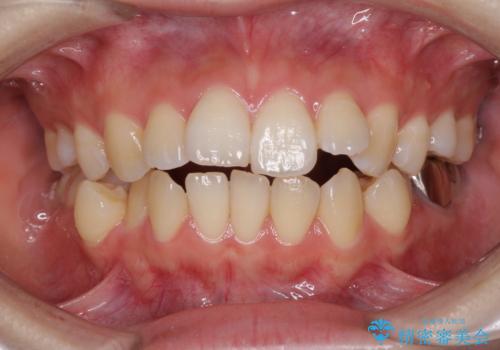

閉じにくい口元と八重歯 ワイヤー装置での抜歯矯正